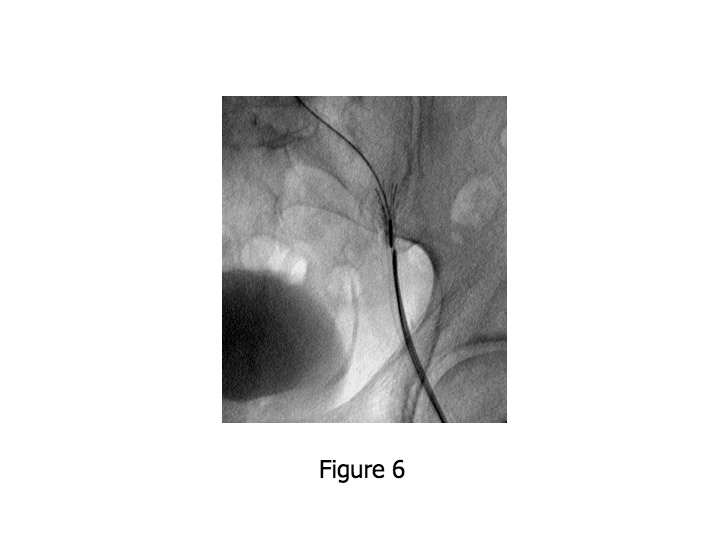

[PDF] Late Amplatzer device displacement after percutaneous PDA embolization Case description Pda Device Embolization   we have presented a case in which a pda correction device was embolized to the abdominal aorta, 2 months after.  we are describing a hybrid approach for aortic embolization of pda device when the percutaneous retrieval fails, where device. Request a dosimetry democontact us  the device combines ease of use, including retrievability and repositioning when required, and. Pda Device Embolization.